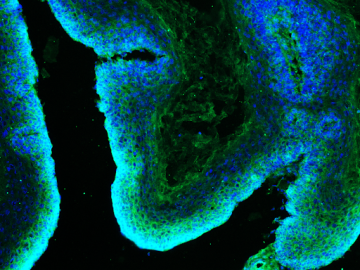

Microscopy image of a skin tumor

Microscopy image of a skin tumor (squamous cell carcinoma), stained with glutamine transporter (ASCT2, green) and nuclei (DAPI, blue). This tumor lacks the enzyme LDHA, which normally helps cells process glucose. Credit: William Lowry Lab/UCLA